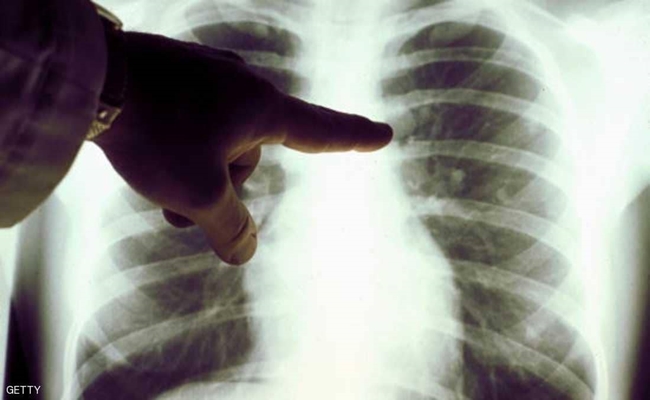

نصائح تقي من جلطة الرئة القاتلة

تعتبر جلطة الرئة من الحالات الطبية الخطيرة حياة الإنسان، حيث إنها تعيق تدفق الدم إلى الرئتين، وبالتالي تقود إلى الموت.

وتحدث جلطة الرئة نتيجة جلطات في الدم تنتقل إلى الرئتين من الساقين، الأمر الذي يسبب انسدادا في أحد الشرايين الرئوية وحدوث ما يسمى بالانسداد الرئوي، وفق ما نقلت قناة “سكاي نيوز” عن موقع “ويب طب”.

تحدث جلطة دموية في شريان معين بالرئتين، وهذه الجلطات الدموية عادة ما تأتي من أوردة الساق العميقة في الساقين، وتعرف هذه الحالة بتجلط الأوردة العميقة (DVT).

وليس بالضرورة أن تحدث جلطات الرئة مرة واحدة، بل يمكن أن تتلف أجزاء من الرئة مع كل انسداد يحدث في الشريان، مما يجعل الأمر أكثر صعوبة على رئة المريض لتوفير الأكسجين لبقية جسمه.